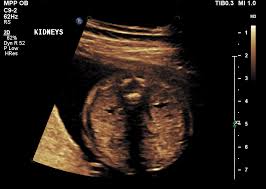

New Born baby with single kidney (Renal agenesis)

New Born baby with one kidney.

What will be the line of treatment for this rare birth defect (disorder)?

• images - 2022-03-16T105434.600.jpeg

images - 2022-03-16T105434.600.jpeg

6.7 KB · Views: 168